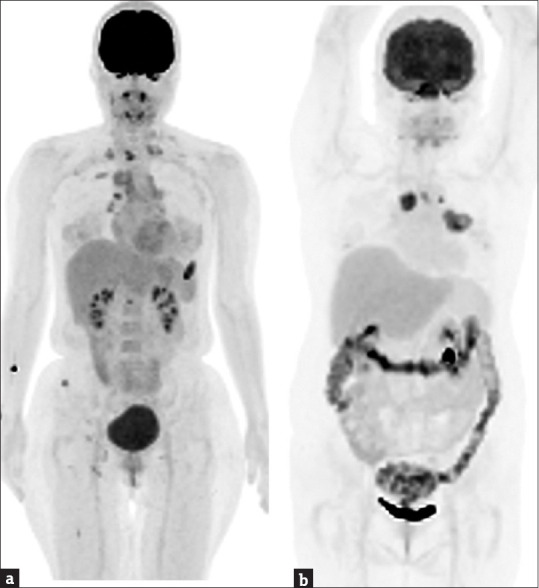

Currently, the second most commonly diagnosed cancer in the world is lung cancer, and 85% of cases are non-small cell lung cancer (NSCLC). With growing knowledge of oncogene drivers and cancer immunology, several novel therapeutics have emerged to improve the prognostic outcomes of NSCLC. However, treatment outcomes remain diverse, and an accurate tool to achieve precision medicine is an unmet need. Radiomics, a method of extracting medical imaging features, is promising for precision medicine. Among all radiomic tools, 18F-fluorodeoxyglucose positron emission tomography (18F-FDG PET)-based radiomics provides distinct information on glycolytic activity and heterogeneity. In this review, we collected relevant literature from PubMed and summarized the various applications of 18F-FDG PET-derived radiomics in improving the detection of metastasis, subtyping histopathologies, characterizing driver mutations, assessing treatment response, and evaluating survival outcomes of NSCLC. Furthermore, we reviewed the values of 18F-FDG PET-based deep learning. Finally, several challenges and caveats exist in the implementation of 18F-FDG PET-based radiomics for NSCLC. Implementing 18F-FDG PET-based radiomics in clinical practice is necessary to ensure reproducibility. Moreover, basic studies elucidating the underlying biological significance of 18F-FDG PET-based radiomics are lacking. Current inadequacies hamper immediate clinical adoption; however, radiomic studies are progressively addressing these issues. 18F-FDG PET-based radiomics remains an invaluable and indispensable aspect of precision medicine for NSCLC.